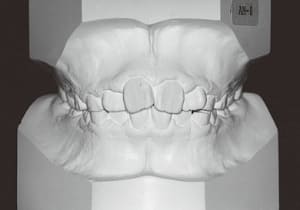

1 Initial Visit 2-11-’88

3 Initial Visit 2-11-’88

4 Initial Visit 2-11-’88

The Class II condition is pronounced, with a significant overjet of 12.5 mm(3). Although the teeth size are large, crowding is relatively mild. The maxillofacial structure has good depth and a robust bone framework(5). The mandible itself is solid , robust gonial angle, but there is significant anterior-posterior displacement relative to the maxilla(ANB 10.0°). While there is no confirmed history of thumb-sucking or similar habits, the lower lip is already pushing up against the maxillary incisors. The cause of this condition is unknown.

The first phase of treatment involved extracting the left and right maxillary deciduous canines. The space created was used to forcibly retract the four anterior teeth, thereby aiming to improve lip closure function (6–9, 11). Morphological changes suggest that lip function differed before and after treatment (6, 9). Subsequently, the first premolars erupted, but extraction is planned to secure space for canine eruption (10). A Class II molar relationship remains, but the significant overjet has improved (11).